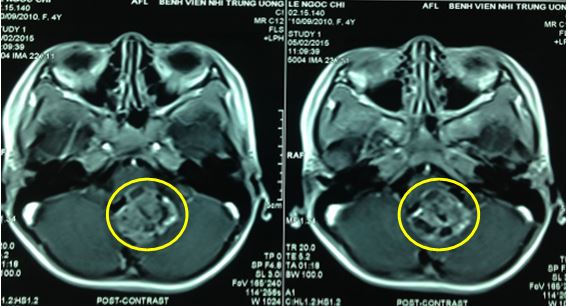

U sao bào - Hình ảnh minh họa

1/4

Click vào ảnh để xem 4 hình ảnh minh họa

Bác sĩ có thể sử dụng hình ảnh cộng hưởng từ (MRI) và chụp cắt lớp (CT) để hỗ trợ trong việc chẩn đoán bệnh một cách chính xác nhất.